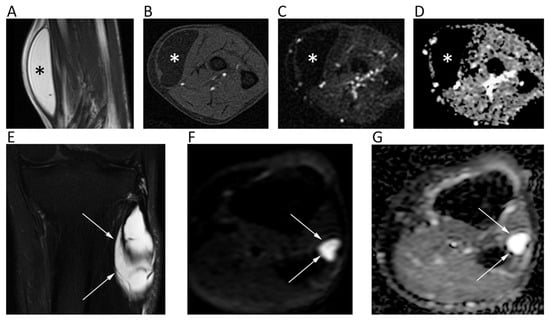

13. Bone Tumors

14. Soft Tissue Tumors

| Bone Tumors | Wang, T.; et al. World J. Surg. Oncol. 2014 [96] | Retrospective; 187 patients; 3.0T MRI. | Mean ADC (×10−3 mm2/s) of benign tumors (1.17 ± 0.36) significantly higher than that of malignant (0.87 ± 0.20). |

| Soft Tissue Tumors | Choi, Y.J.; et al. J. Magn. Reson. Imaging 2019 [107] | Retrospective; 136 patients; 3.0T MRI. | Significant difference between mean ADC (×10−3 mm2/s) of benign (1.44 ± 0.46) and malignant (0.9 ± 0.40) soft tissue tumors. |